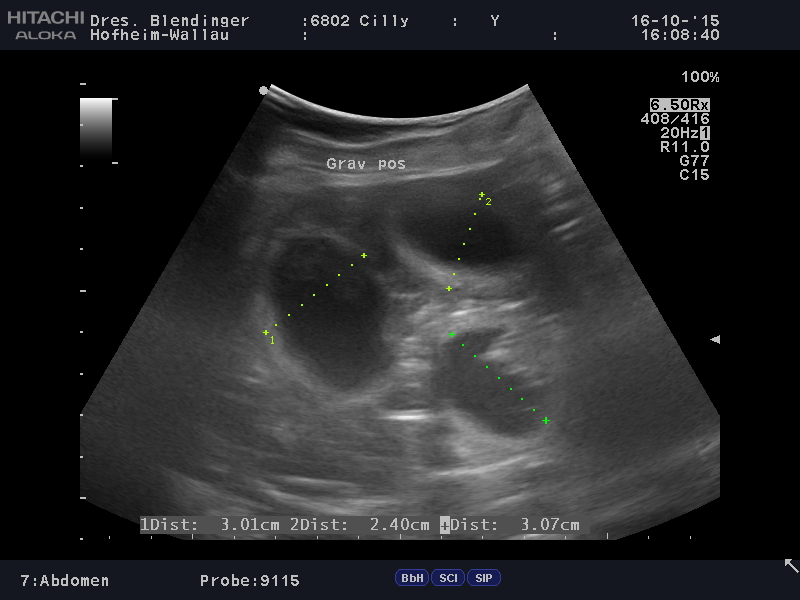

Cillys zweiter Wurf!

Wurftag:  16.11.2015

Mutter: Cilly-Cinderella vom Mönchswald, ZBNr.: 24575